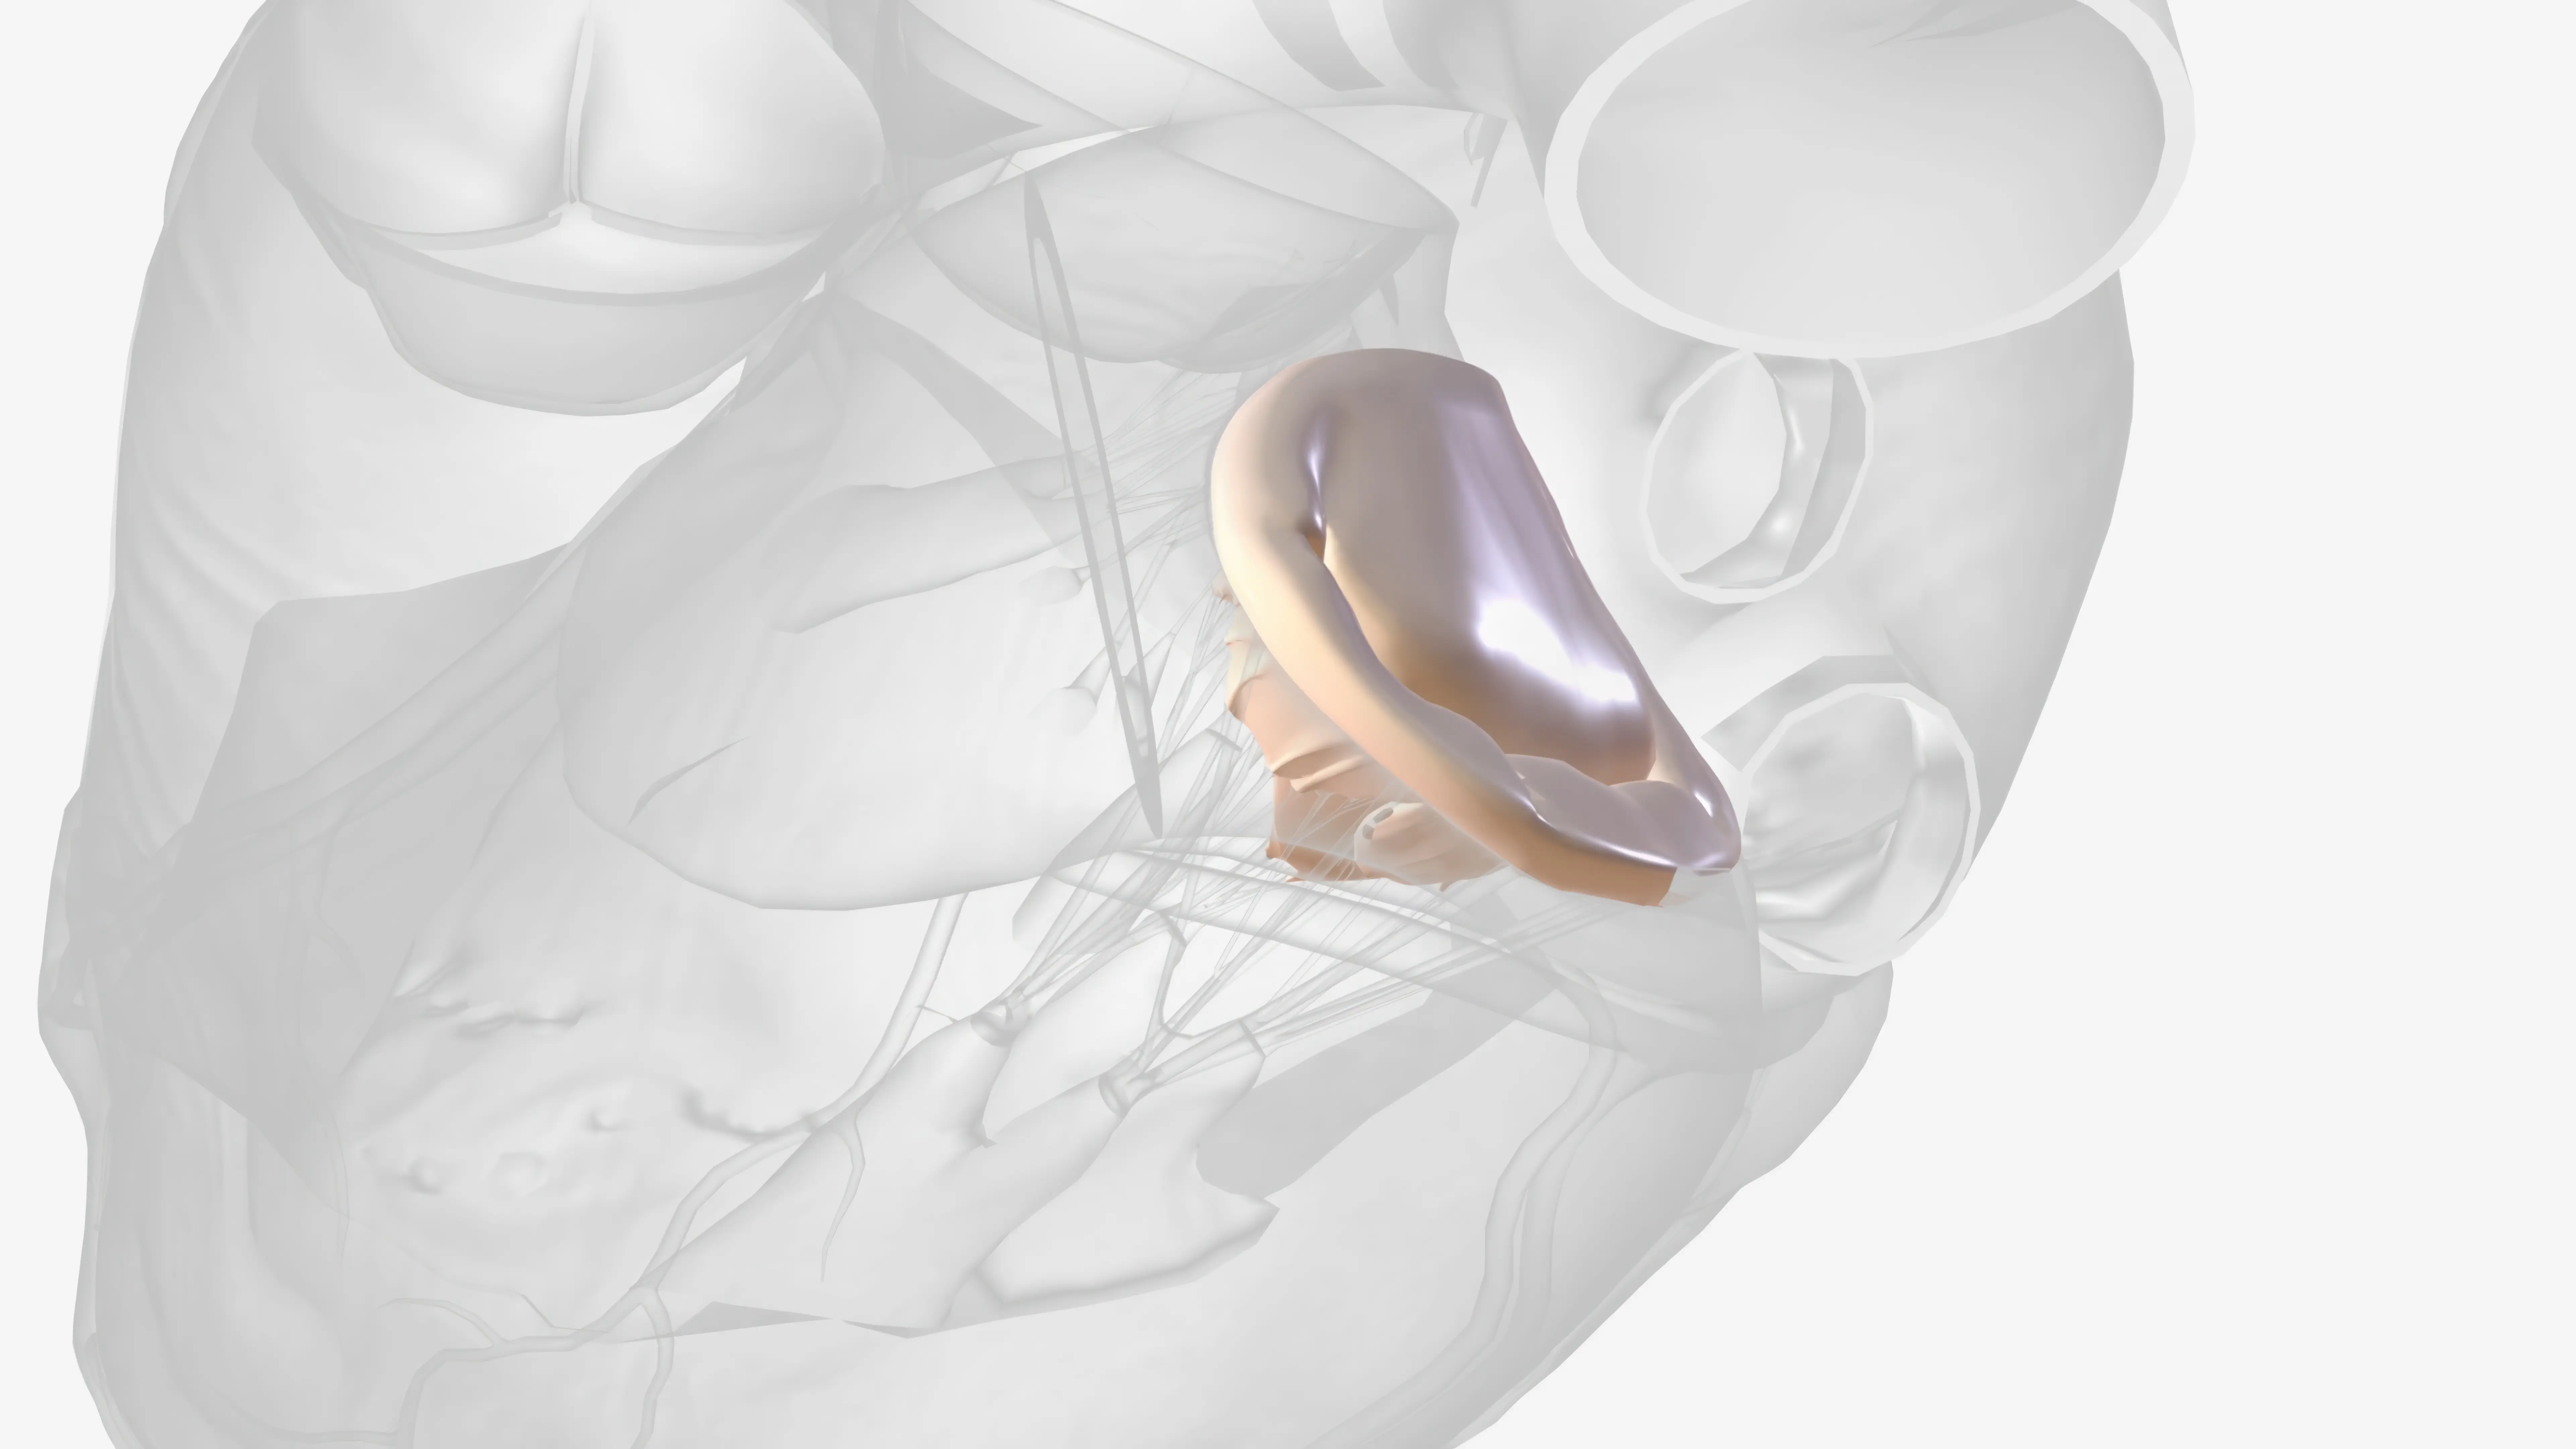

Kapalı Kalp Ameliyatı ile Kalp Tümörü (Mixoma) Ameliyatı

Kalpte ortaya çıkan primer tümörler oldukça nadirdir; otopsilerde rastlantısal olarak saptanma oranı %0,0017 ile %0,19 arasında değişmektedi...